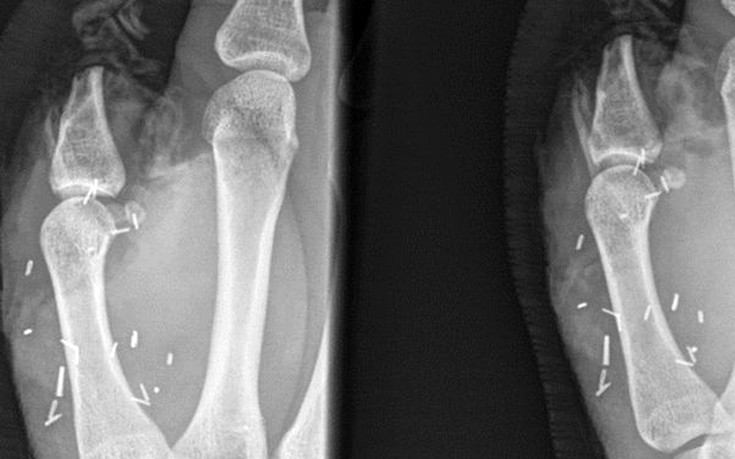

Ο 20χρονος υποβλήθηκε σε δύο επεμβάσεις για την επανατοποθέτησή του, που όμως δεν πέτυχαν. Έτσι οι γιατροί, όπως γράφει το BBC, αποφάσισαν να τοποθετήσουν στη θέση του αντίχειρα το μεγάλο δάχτυλο του ποδιού του. Η επέμβαση έγινε πριν από δύο εβδομάδες σε νοσοκομείο του Σίδνεϊ και κράτησε οκτώ ώρες.